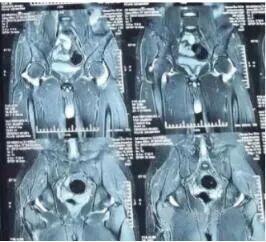

同年4月份大腿内外侧和腹股沟区均出现疼痛,且左下肢跛行,在家人的陪伴下,遂前往市专科医院,经系统专项检查:x片显示骶髂关节炎侵犯双侧髋关节,磁共振检查显示髋关节积液,诊断为骶髂关节炎、髋关节滑膜炎。

双侧骶髂关节密度不均,关节间隙似乎不等、双侧髋关节包容欠佳,从磁共振上看关节内大量积液

诊断明晰了,下一步治疗就可分疾病的轻重缓急顺序进行。首先从病因上治疗骶髂关节炎,以改善髋关节滑膜炎症状,远期对于双侧股骨头的影响也不容忽视,需要定期观察!